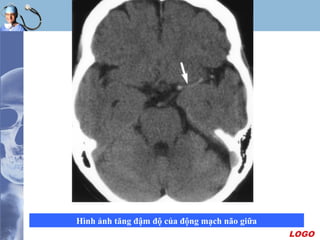

Tìm dấu hiệu huyết khối trong lòng mạch

 Dấu hiệu tăng đậm độ của động mạch do huyết khối

trong lòng mạch máu, gặp tại :

- Động mạch não giữa và các nhánh ( Dot sign )

- Nơi tận cùng động mạch cảnh trong

- Động mạch thân nền

 Ðây là một triệu chứng tiên lượng nặng vì vùng nhồi

máu lớn

 Tuy nhiên cần lưu ý trong trường hợp triệu chứng xuất

hiện đối xứng hai bên ( vôi hóa ), bên có huyết khối

phải tăng quang nhiều hơn.

LOGO

Hình ảnh tăng đậm độ của động mạch não giữa